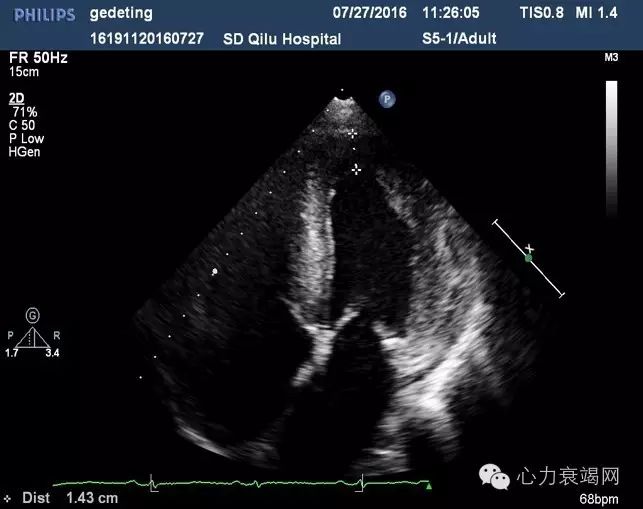

【辅助检查】—心脏超声

IVS 15mm,LVPW 14mm

LVEF 37%

肺动脉高压(中度)

E/e’=21舒张功能减低

提示:心肌病变(病因请结合临床)

IVS 15mm,LVPW 14mm,左室侧壁15mm 心尖部13mm;左室心肌回声不均匀;LVEF 35% ,双房扩大,肺动脉高压(中度)E/e’=21 舒张功能减低

提示:心肌病变淀粉样变心肌病待排?

▶左右心室腔偏小,左心室后壁及心室间隔增厚,心肌回声呈毛玻璃样,室壁运动僵直,双心房扩大

▶心房壁、房间隔及心脏瓣膜也不同程度的增厚

▶舒张功能指标减低